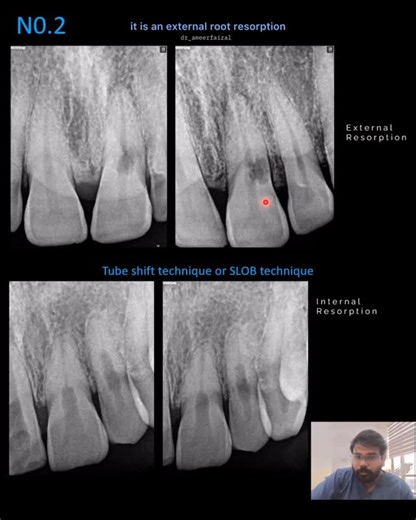

- Resorption

Root Resorption - Resorption

Resorption - External Root Resorption